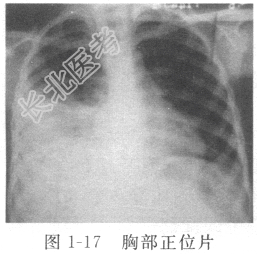

/L,N% 70.1%,L% 19.4%。口服双黄连口服液及解热镇痛片后,胸痛逐渐减轻,但体温仍未恢复正常,胸闷较前加重,遂就诊我院。查体:消瘦体型,右侧语音震颤减弱,右侧呼吸音减弱,心脏、腹部体检无异常。门诊胸部X线片(图1-17)示右侧胸腔积液,血沉70mm/h,PPD试验(+++),拟“胸腔积液”收入科。入院初步诊断:右侧胸腔积液(原因待查)。

患者中年女性,农民,病程不长,起病隐匿,有咳嗽、胸痛、胸闷等呼吸道症状,有午后低热、盗汗、乏力等全身中毒症状,胸部X线片示右侧胸腔积液,ESR偏快,考虑胸腔积液原因为结核性可能性大。入院后行胸腔穿刺,引出草黄色透明胸水600ml。胸水常规示李凡他试验阳性,比重1.018,白细胞1.28×10